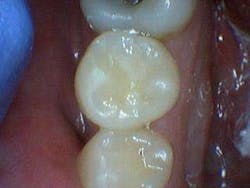

After the final smear layer was removed, the tooth was filled with Grandio resin. Afterwards, I showed the photographs to my patient. Any doubt that he had was immediately erased. Most importantly, he was grateful and his trust in me was solidified.